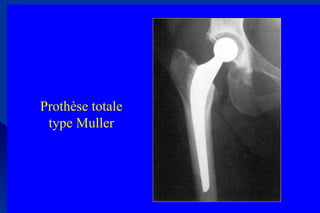

Des arthroses évoluéesDes arthroses évoluées

- arthroplastie totale de hanche- arthroplastie totale de hanche

- après échec du tt médical bien conduit- après échec du tt médical bien conduit

arthroplastie totale si gène fonctionnelle importantearthroplastie totale si gène fonctionnelle importante

indice de Lequesneindice de Lequesne > 10 ou 12.> 10 ou 12.

Prothèse totale

type Muller